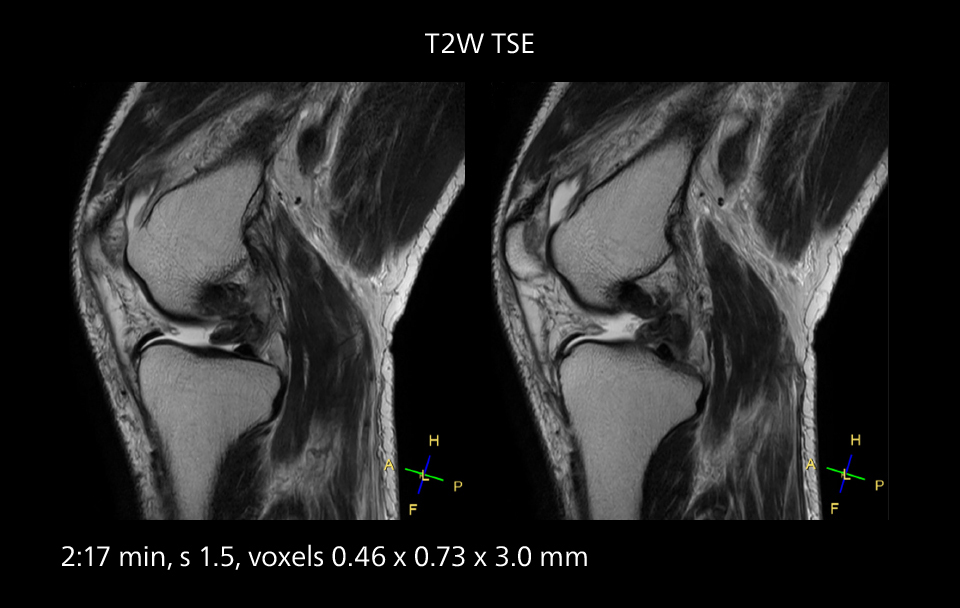

An example of increased imaging speed is in knee studies. “There is a definite scan time reduction for T2* mFFE and proton density TSE – both of these sequences benefit from much shorter repetition times,” he reports.

MRI of the knee

Images showing a posterior cruciate ligament (PCL) tear, a detached medial collateral ligament (MCL) on the tibial side and an intact anterior cruciate ligament (ACL). SmartPath to Elition X helped reduce scan time compared to previous imaging while maintaining resolution.

Overall, imaging time per sequence has been reduced since the Elition X upgrade. This can help reduce the risk of patient movement and the need for rescans.